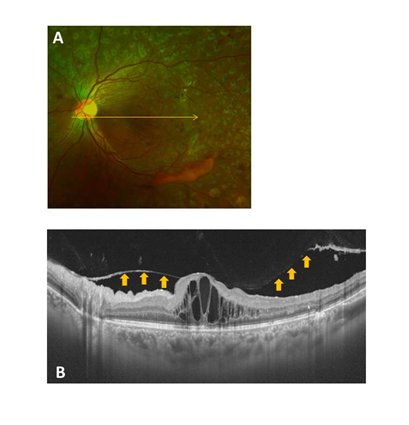

The OCT images of the eyes were obtained at the initial patient visit by SS-OCT (DRI OCT-1 Atlantis, Topcon, Tokyo, Japan) and used to investigate the posterior wall of the PPVP. This particular OCT system has an A-scan repetition rate of 100,000 Hz, with a light source that operates in the 1-μm wavelength region. The light source consists of a wavelength-tunable laser centered at 1,050 nm with a 100 nm tuning range. This system used an 8μm axial resolution and a 20 μm lateral resolution, with a 2.3 mm imaging depth in the tissue. The ocular fundus was examined by performing 12 mm horizontal and vertical scans through the fovea. Based on these scans, the condition of the posterior wall of the PPVP was classified into the following four groups: Group 1, no PVDs (Figure 1); Group 2, perifoveal PVD (Figure 2); Group 3 macular PVD (Figure 3); and Group 4, complete PVD (Figure 4).

Figure 1 Representative fundus photo and OCT image for a Group 1 (no PVD) case (A and B). The condition of the posterior wall of the PPVP is indicated by the arrows.